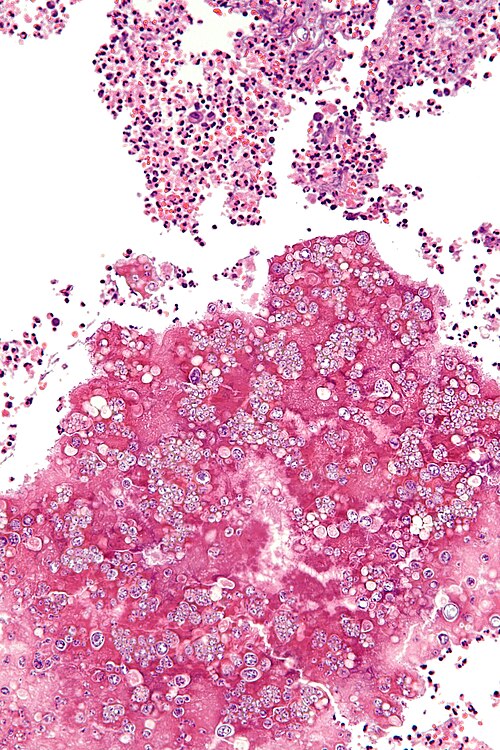

High magnification

High magnification. H&E stain.

Patient also has a headache, rash, myalgias, and arthralgias. HIV positive. Lives in San Francisco part of the year.

Looks like an infection. Did you do a GMS? Looks like there are large spherules (60-80 micrometres in size) with (1-5 micrometres) endospores.